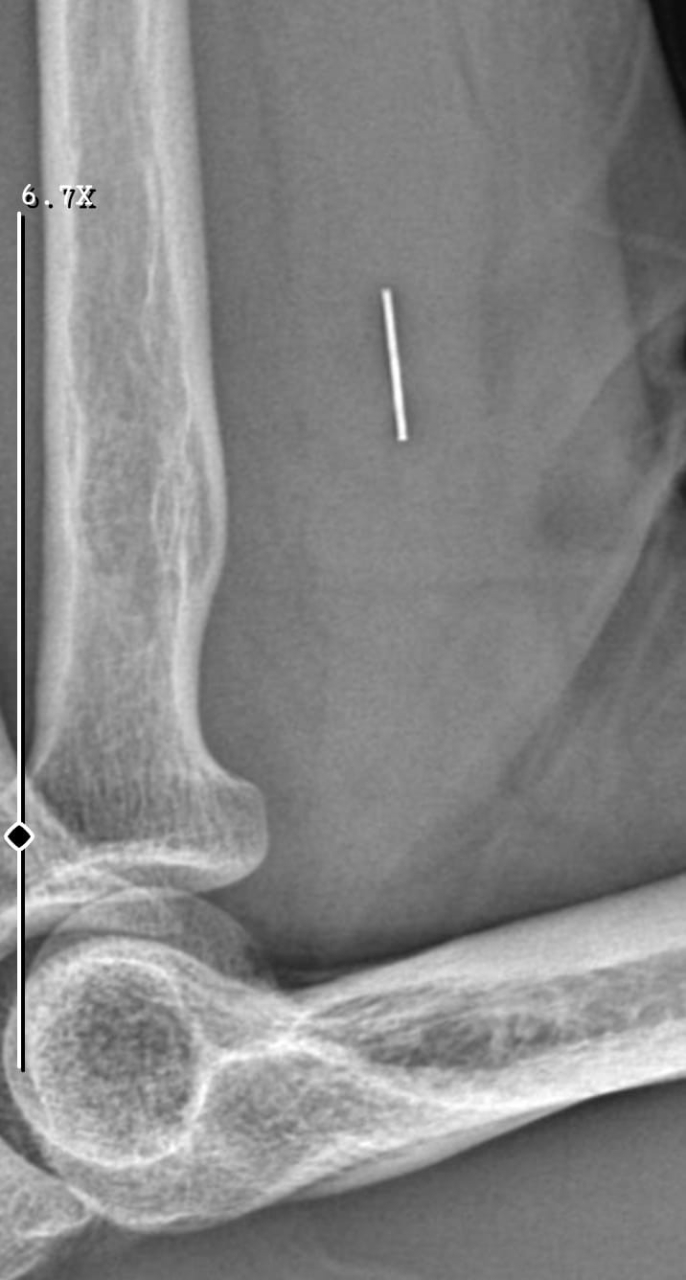

Edinilen bilgilere göre, 7 Haziran 2025'te Kurban Bayramı dolayısıyla bıçak temizlerken sağ el başparmağını kesen Güleryüz (34), ilk olarak bir özel hastanenin acil servisine başvurdu. Ancak hastanede detaylı tetkik yapılmadan yalnızca pansuman yapılarak taburcu edildi. Şikayetleri devam eden Güleryüz, ertesi gün tekrar aynı hastaneye gittiğinde dikiş atıldı. Parmağının hareket etmemesi üzerine 19 Haziran'da başka bir özel hastaneye başvurdu ve burada tendon yaralanması şüphesiyle tedaviye alındı. Yapılan tetkiklerde sinir hasarı ve tendon kopması tespit edilince, 2 Eylül'de ameliyat oldu. Ancak süreç içinde parmağın çürüdüğü belirtilerek ampute edilmesi gerekti.